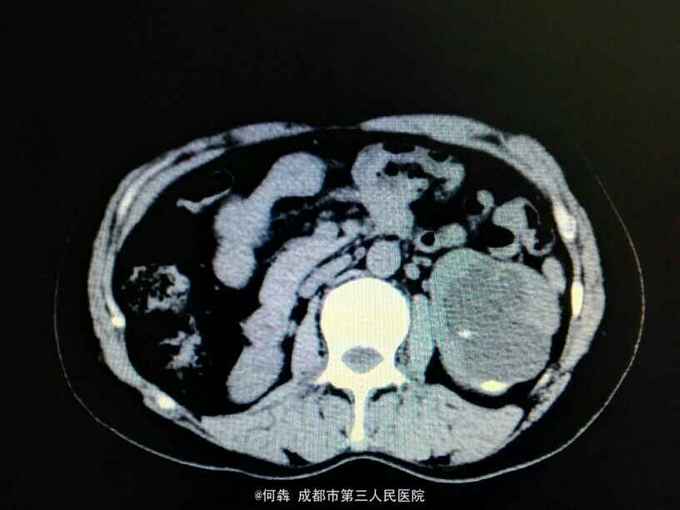

左肾区轻叩痛。尿常规:白细胞72个/ul。CT见图片。左侧GFR42.27,右侧GFR14.46。

左肾盂输尿管交界处结石 左肾重度积水,左肾结石,右肾萎缩,尿路感染。